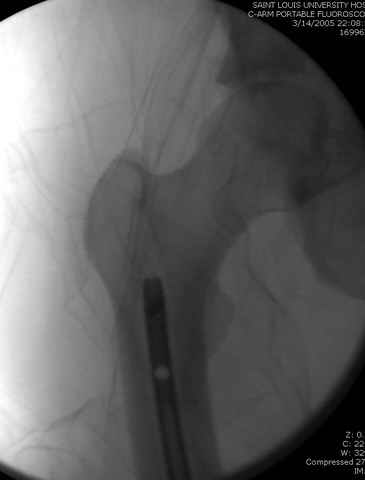

33 yo male motocross rider crashed after a jump sustaining isolated bilateral femur fxs, R side with a basicervical femoral neck and ipsilateral mid-distal 1/3 shaft, L side with a subtroch/prox 1/3 femur fx. Pt was HD stable, no LOC, GCS - 15, No other injuries, spines cleared.

The most critical injury is the proximal fracture on the right.

Retrograde nail right femur being careful that you don't knock off the neck fx.

DHS with de-rotation screw for neck (make sure you carefully tap the screw path so as not to spin off the reduction when the screw purchases, possible

even with a derotation screw) and use a plate that overlaps your nail (can put plate screws around nail, or through a locking hole). Alternatively, the synthes locking proximal femoral plate could be used.

Sequence ­ Right neck, right shaft, then left shaft.

Implants ­ plenty of opinions exist for the right side...some would use neck screws anteriorly after reduction, then with a slender reamed locked nail

pushed in behind the neck screws for the shaft... some will advocate a recon nail for both...some will use a sliding screw for the neck then a retrograde shaft nail...some would use the sliding neck screw and a shaft plate also...lots of options.

I prefer excellent neck reduction either closed or open, screws high and low anteriorly for it, then a frail locked nail slipped in behind the neck screws for the shaft.